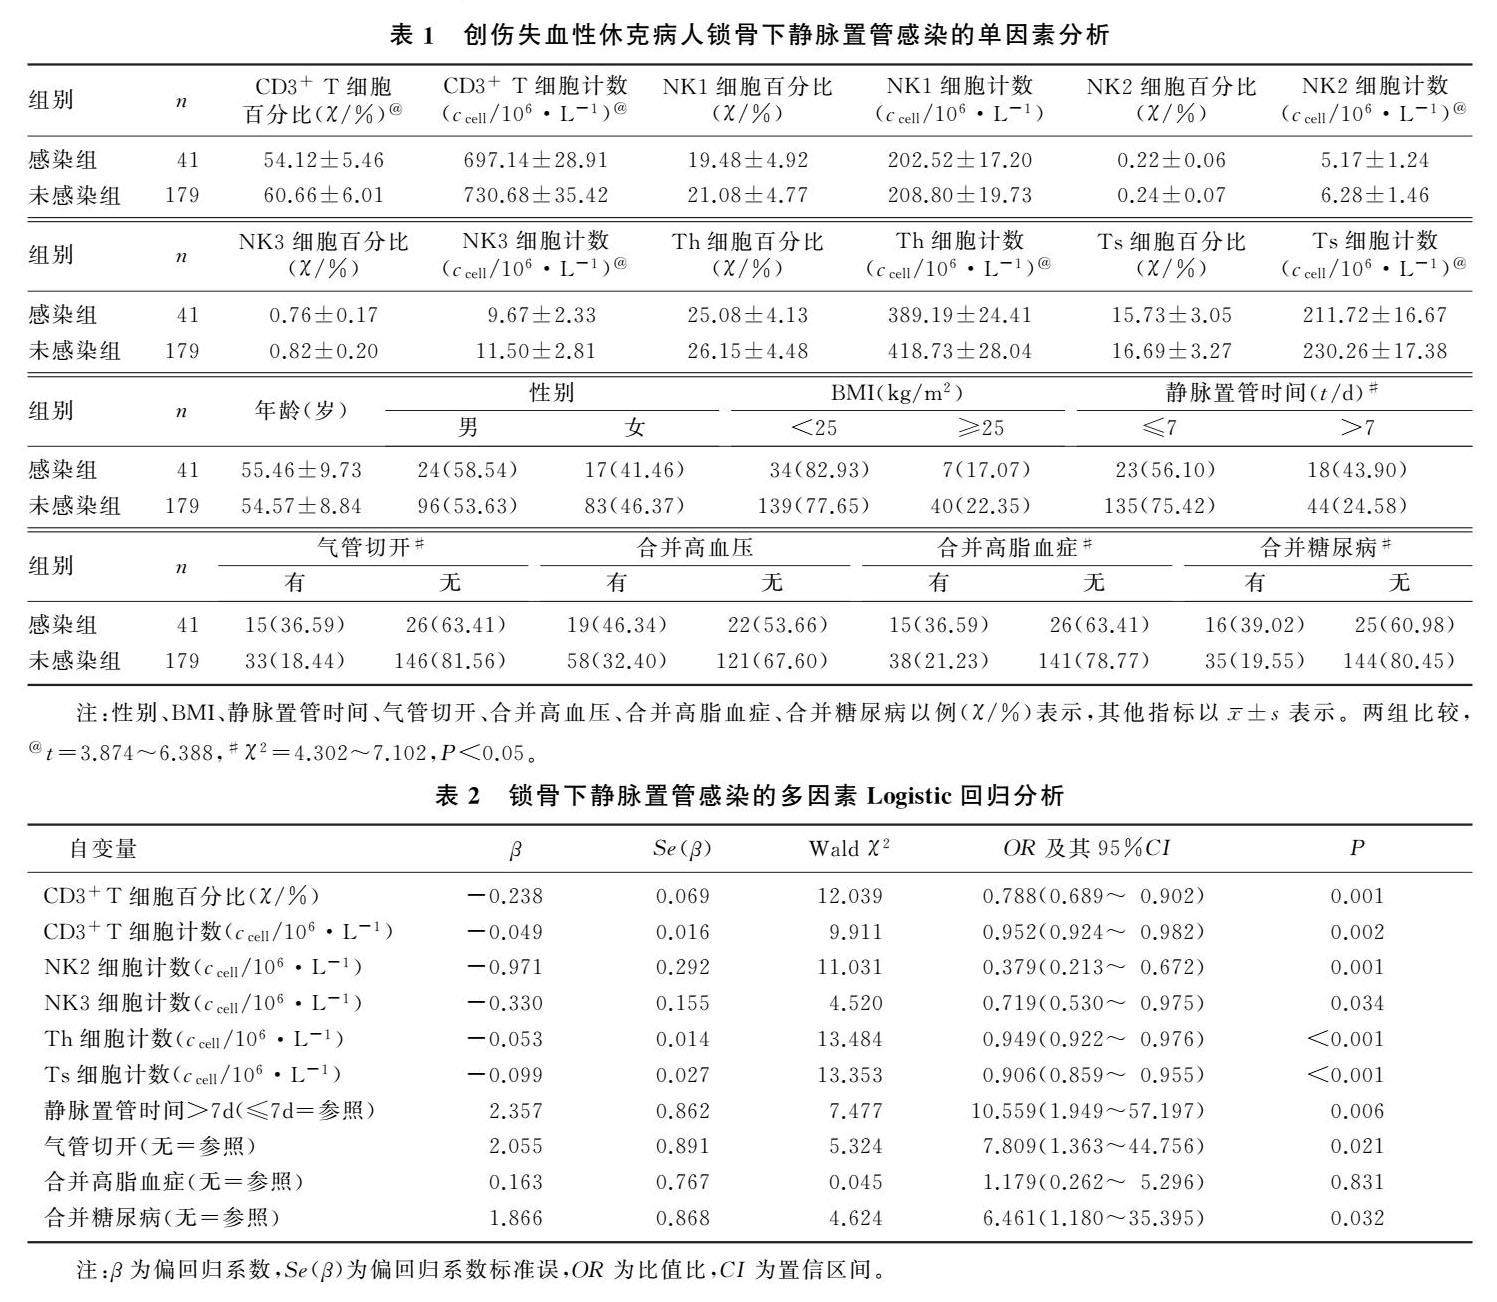

论著 | 外周血免疫细胞计数与创伤失血性休克病人锁骨下静脉置管感染的相关性

论著 | 外周血免疫细胞计数与创伤失血性休克病人锁骨下静脉置管感染的相关性